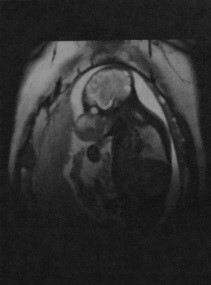

(а) Т1 МРТ с гадолинием, фронтальный срез. Холестероловая гранулема, распространяющаяся из сосцевидного отростка в левую височную долю (стрелка).

(б) МРТ в аксиальной проекции в режиме Т2. Обратите внимание на то, что сигнал повышен и на Т1, и на Т2 (стрелка).